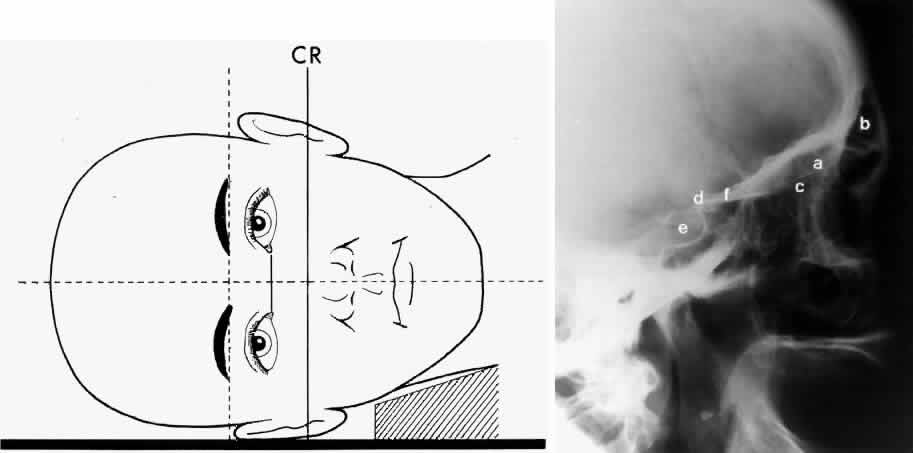

Lateral projection (Fig. 4) is created by placing the patient's head against the x-ray cassette and centering the cassette on the lateral canthus. The x-ray beam is directed perpendicularly to the midpoint of the cassette and enters the patient's head at the lateral canthus remote from the cassette.5,6 This projection provides a view of the sagittal plane of the skull. Because of the overlapping skeletal structures, interpretation of unilateral disease processes is difficult. The structures that can be identified and best evaluated include the sphenoid, frontal, ethmoid, and maxillary sinuses. This lateral view also shows the sella turcica, the anterior and posterior clinoid processes, the nasopharynx, and the cribriform plate. The orbital structure best evaluated is the orbital roof. The floor of the orbit is visible but evaluation is difficult because of the upward slope, from lateral to medial, toward the orbital apex. This slope causes the floor to appear at different levels on the lateral view.11 The lateral projection, although not as useful as the frontal projections, gives information concerning air-fluid levels in traumatized patients, when only a horizontal projection is possible.

Fig. 4. A. Schematic showing positioning for a lateral projection. (CR, central ray) B. Radiograph of a lateral projection. (a, orbital roof; b, frontal sinus; c, ethmoid sinus; d, anterior clinoid process; e, sella turcica; f, planum sphenoidale) (A; Rao VM, Gonzalez CF: Plain film radiography and polytomography of the orbit. In Gonzalez CF, Becker MH, Flanagan JC [eds]: Diagnostic Imaging in Ophthalmology, pp 1–7. New York, Springer Verlag, 1986)

BASAL PROJECTION (SUBMENTO-VERTEX)

The basal projection (Fig. 5) for the evaluation of the sphenoid sinus and skull base was described initially by Arthur Schuller12 in 1905 and later popularized in this country by Bowen.13 This projection is obtained with the patient's neck extended either in the supine or upright position. The top of the head is placed so that the infraorbitomeatal line is parallel with the x-ray cassette. The x-ray beam is directed at right angles to the infraorbitomeatal line.5,6 This view shows the lateral walls of the orbit and maxillary sinuses well. The nasopharynx, pterygoid plates, pterygopalatine fossa, and the sphenoid and ethmoid sinuses may also be inspected. Because of the extreme head position, any history of a neck injury is a contraindication to this radiologic study.

Fig. 5. A. Schematic showing positioning for a basal projection. (CR, central ray; IM, infraorbitomeatal line) B. Radiograph of a basal projection. (a, zygomatic arch; b, orbit; c, lateral orbital wall; d, posterior wall of maxillary sinus; e, pterygoid plate; f, sphenoid sinus) (A; Rao VM, Gonzalez CF: Plain film radiography and polytomography of the orbit. In Gonzalez CF, Becker MH, Flanagan JC [eds]: Diagnostic Imaging in Ophthalmology, pp 1–7. New York, Springer Verlag, 1986)